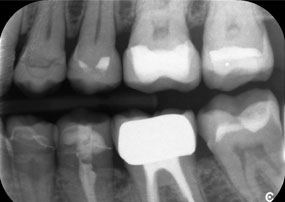

Le défi consistait à retirer douze couronnes splintées en alliage métallique sans endommager les dents piliers sous-jacentes. La pièce à main a été utilisée pour sectionner avec précision les couches de céramique et diviser l'armature métallique à l'aide d'une fraise au carbure, ce qui a permis un retrait minimalement traumatisant des couronnes. En seulement 30 minutes, les anciennes restaurations ont été retirées, permettant la préparation d'une nouvelle prothèse, composée de zircone à contour complet dans la région postérieure et de couronnes facettées dans la région antérieure. Le résultat a été une restauration complète qui a permis d'obtenir un succès tant fonctionnel qu'esthétique (voir fig. 1).

Un deuxième cas illustrant les capacités cliniques du Power Edition concernait le remplacement d'une couronne en zircone endommagée chez une patiente de 63 ans. La patiente présentait une facette ébréchée sur sa couronne en zircone vieille de 20 ans sur la dent 6. Malgré l'emplacement postérieur, la patiente trouvait le défaut gênant et demandait une nouvelle restauration.

Le Power Edition a permis un sectionnement précis, grâce à un couple accru et un refroidissement amélioré qui ont contribué à l'ablation contrôlée de la couronne sans perte importante de matière. Le système de serrage et le couple amélioré se sont avérés essentiels dans ce processus.